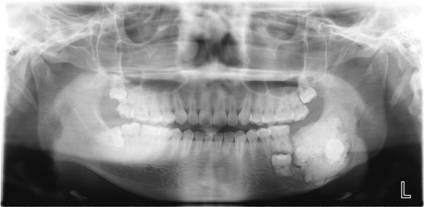

常规开展:数字化根尖片/横断牙合片、数字化口腔曲面体层片、头影测量侧位/正位片、手腕骨片、颅颌面CBCT、牙齿CBCT的检查以及涎腺造影、窦道 瘘管造影。

数字化口腔曲面体层片